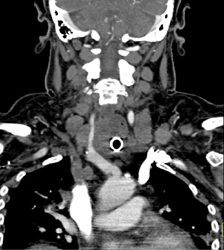

Takayasu's Arteritis